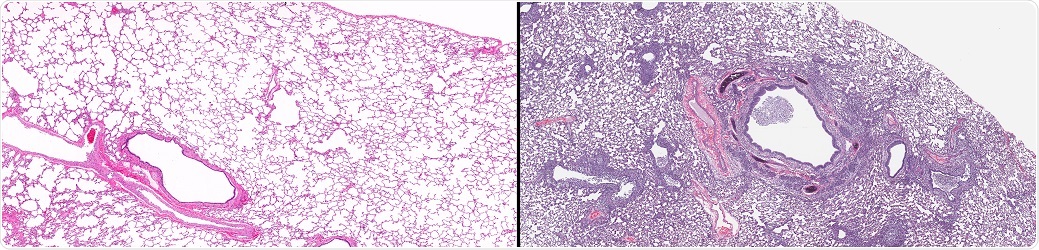

Normal Lung (left) and Lung with Influenza (right). Comparative twin images of normal healthy lung in contrast to lung from a case of influenza showing microscopic disease pathology of flu. © vetpathologist / Shutterstock.com.